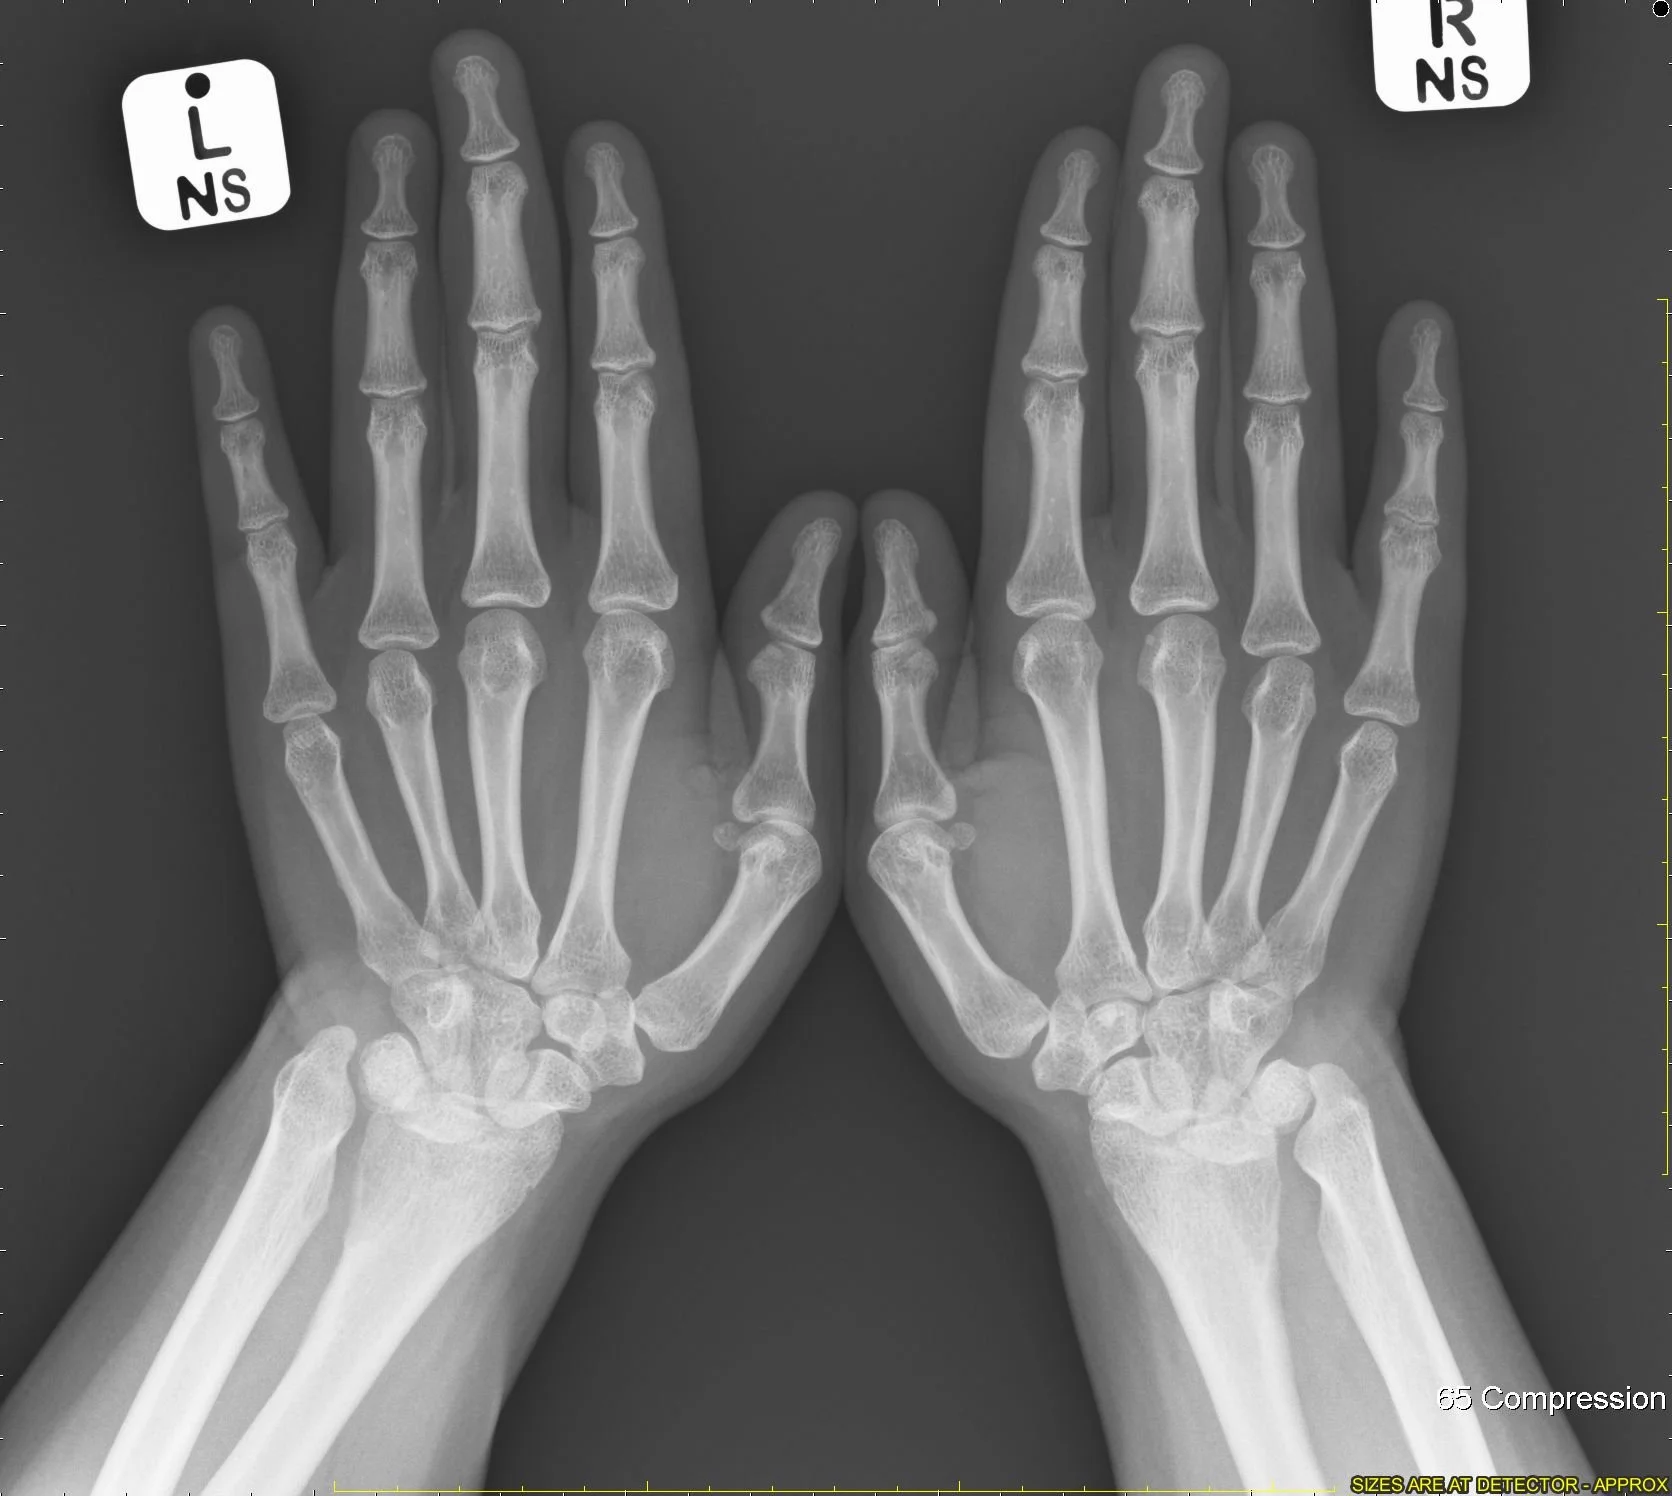

Madelung Deformity

• Basically a sloped appearance of the distal radius

• Bowing of radial shaft with increased interosseous space + dorsal subluxation of DRUJ

• Caused by early closure/issue with distal radial physis

• Seen at age 10-14

• Congenital or post-traumatic

• Vickers ligament is a ligament that connects the lunate & TFCC to distal radius and is seen in Madelung deformity and may be cause of worsening symptoms of release has been shown to improve symptoms

• Case courtesy of Naim Qaqish, Radiopaedia.org, rID: 81737 (madelung)

• Case courtesy of Ashesh Ishwarlal Ranchod, Radiopaedia.org, rID: 89839 (madelung)